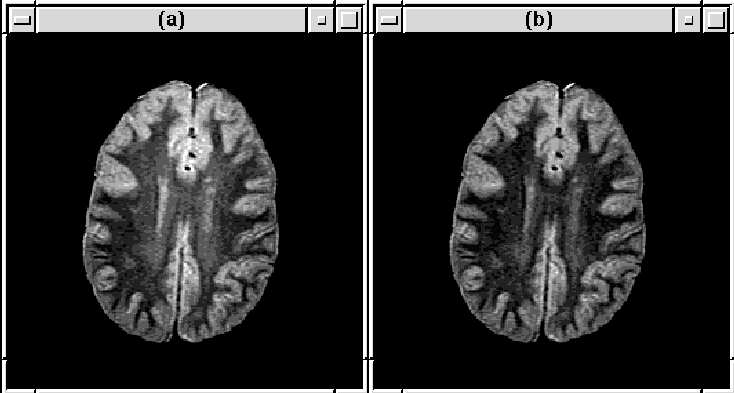

Figure 8.27: Slice 16 of MRI Data Set 1 (a) before

and (b) after RF correction.